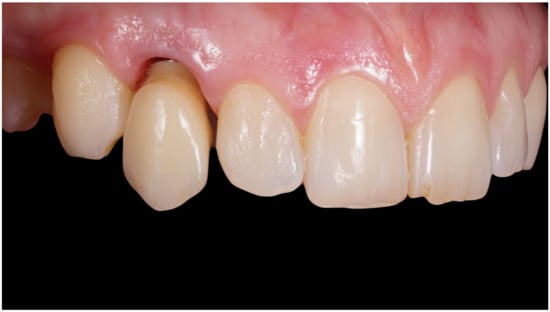

Figure 2.

Lateral preoperative view.

Figure 6.

Healing of soft tissues around the temporary crown.